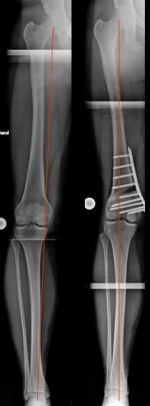

Beispiel einer aufklappenden Osteotomie, kniegelenksnah, am Schienbein bei O-Beinfehlstellung. Die MA wurde zentriert, da noch keine Schädigung des Gelenkes vorlag (Bild 2).